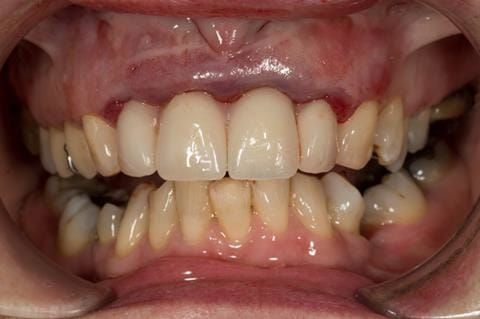

- High smile line showing gum above gingival zeniths of upper front teeth when smiling. Aesthetic failure of the upper four incisors with inflammation of the gingivae and mis-match of the gingival zenith levels.

- Extract the upper 2-2 teeth and replace with an interim acrylic based partial denture. Reline the interim denture over 9 - 12 months, replacing with a definitive cobalt chromium based partial denture. The definitive denture would ideally be designed as an occlusal protective splint to reduce the the potential for mechanical wear and breakages of the moderately/heavily restored maxillary dentition. In addition, should further upper teeth require extraction they could be added on to the denture cobalt chromium framework - therefore a new prosthesis would not be required as future teeth are lost. This option would produce an excellent aesthetic outcome. This is the option the patient chose to have.

Following consultation and second discussion appointment the patient chose to have option 3 namely, a maxillary cobalt chromium based partial denture/protective occlusal splint. The clinical situation and treatment process is shown in detail below with photographs. The patient was successfully rehabilitated with this and her quality of life considerably improved. The clinical work was provided by Finlay and the technical work by Rowan.